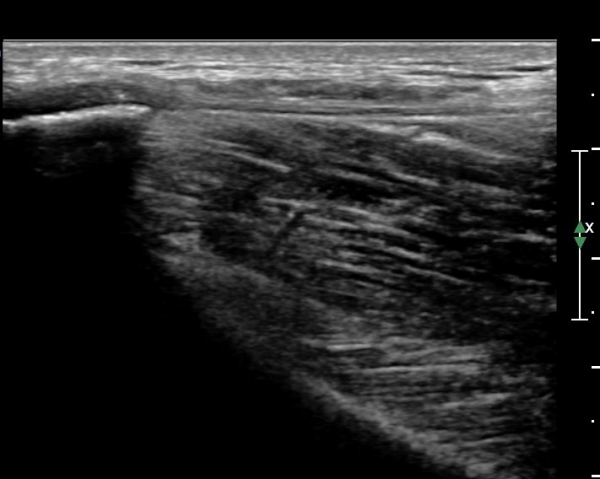

ÃÊÀ½ÆÄ°Ë»ç: °í°üÀý ¾ÕÂÊ Á¾´Ü¸é °Ë»ç¿¡¼­ °üÀý³¶ÀÌ µÎ²¨¿öÁö°í °æ¹ÌÇÑ °üÀý³» ºÎÁ¾À» º¸ÀÓ(»çÁø1, 2)